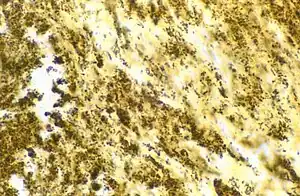

| Bartonella henselae bacilli in cardiac valve of a patient with blood culture-negative endocarditis. The bacilli appear as black granulations. | |